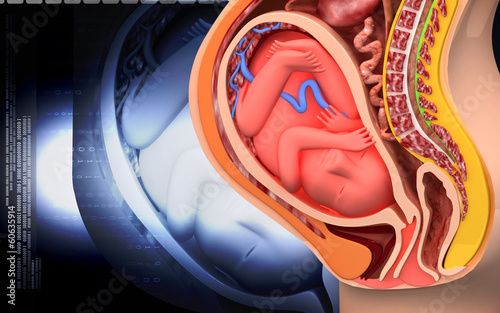

Физиология беременности: строение органов

Раздел: Моменты озарения